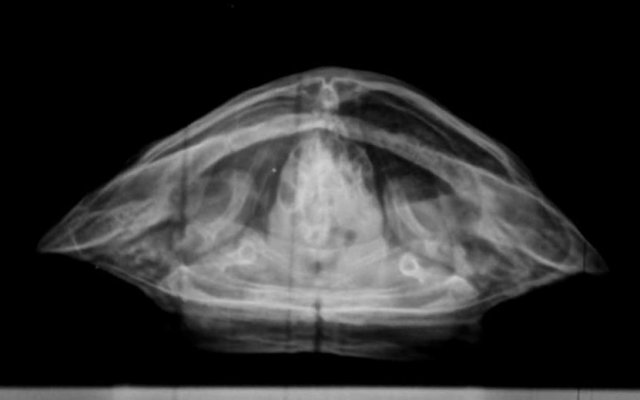

Алексей Alex-Raduga Ваше имя: Алексей Локация: Россия, МО, Серпуховский район Опубликовано: 31 января 2024 Автор Опубликовано: 31 января 2024 @moth здравствуйте ! Сегодня возил на рентген, сделали все проекции, Савина сказала - возможно пневмония, назначила антибиотик энрофлоксацин 2,5%, по 0,12мл 3-4 раза через день и элеовит 0,18мл. - 2 раза с интервалом в 14 дней. Также остается эспусмизан еще 14-21 день (21 день уже его давал, с кормом раз в 3 дня). Также назначила взять анализ кала. Если не пройдет - сказала везти на КТ. Все верно, больше ничего пока не нужно ?

Консультанты moth Ваше имя: Мария Локация: Москва Опубликовано: 31 января 2024 Консультанты Опубликовано: 31 января 2024 @Алексей Alex-Raduga да, всё верно одно лёгкое мутное совсем, жалко тогда она не стала другие проекции делать. А Элеовит ему делали раньше?

Консультанты moth Ваше имя: Мария Локация: Москва Опубликовано: 8 февраля 2024 Консультанты Опубликовано: 8 февраля 2024 @Алексей Alex-Raduga она сказала, что тут однозначно кт нужно. Либо лёгкое схлопнулось, либо сильная односторонняя пневмония. Трава с мостика такое бы не вызвала.

Алексей Alex-Raduga Ваше имя: Алексей Локация: Россия, МО, Серпуховский район Опубликовано: 15 февраля 2024 Автор Опубликовано: 15 февраля 2024 (изменено) Результаты Кт : Протокол КТ Информация по животному Тотоша ,рептилия ,Черепаха красноухая. Протокол ДЫХАТЕЛЬНЫЕ ПУТИ - Визуализируется короткая трахея, разделяющаяся на два бронха, делающие изгиб в дорсальном направлении и входящие в легкие. Правое легкое имеет типичный сегментированный многокамерный вид, пневматизировано, имеет ретикулярный и "сотовый" рисунок, определяется умеренное утолщение перегородок. Бронх левого легкого частично пневматизирован, на остальном протяжении заполнен мягкотканым патологическим содержимым. Левое легкое уменьшено (25х16х12 мм), безвоздушно, паренхима уплотнена до мягкотканых значений, перфузия сохранена, слабо неравномерная. КОСТНЫЕ СТРУКТУРЫ - без патологических изменений. СЕРДЦЕ - без патологических изменений. ПЕЧЕНЬ - без патологических изменений. ЖЕЛЧНЫЙ ПУЗЫРЬ - в правой доле печени, грушевидной формы, умеренно наполнен однородным жидкостным содержимым. СЕЛЕЗЕНКА - овальной формы, 12 мм, расположена дорсо-медиально от желудка. ПОДЖЕЛУДОЧНАЯ ЖЕЛЕЗА - не визуализируется. ЖЕЛУДОК - не наполнен, стенки не утолщены. КИШЕЧНИК - содержит минимальное количество химуса и газ, стенки не утолщены. ПОЧКИ - локализованы в дорсальной части каудального целома, структура и перфузия не изменены. МОЧЕВОЙ ПУЗЫРЬ - умеренно наполнен, стенки не изменены. ПОЛОВЫЕ ОРГАНЫ - не визуализируются. Заключение Заключение: КТ-признаки тотальной левосторонней пневмонии. Обструкция левого бронха. Информация по животномуТотоша ,рептилия ,Черепаха красноухая Анамнез: В мире животнрых (Серпухов) Савина Ярослава Игоревна Жалоба - в течении месяца всплывает на одну сторону (правую). Бывли в сторонней клинике - назначили антибиотик, газасвязывающий препарат, витамины. Активность - норма. Аппетит - норма. Дефекация - норма. Кормление - корм для черепах. Содержание - аквариум, вода 26-27 гр, мостик, УФ лампа и лампа нагрева. Объективно: Общее состояние - удовлетворительное на момент осмотра. Ментальный статус - ясный. Дегидратация - не выражена. Глаза - чистые. Носовые ходы - чистые. Ротовая полость - без патологий. ВСО - бледно-розовые. Состояние кожного покрова и панциря - линька. Упитанность - норма. М - 272 гр. Диагнозы: Предварительный диагноз: Пневмония Врач: Ложечко Анастасия Леонидовна А НАЗНАЧЕНИЙ НЕТ ! Чем лечить-то ? Продолжить уколы энрофлоксацина ? Изменено 15 февраля 2024 пользователем Алексей Alex-Raduga